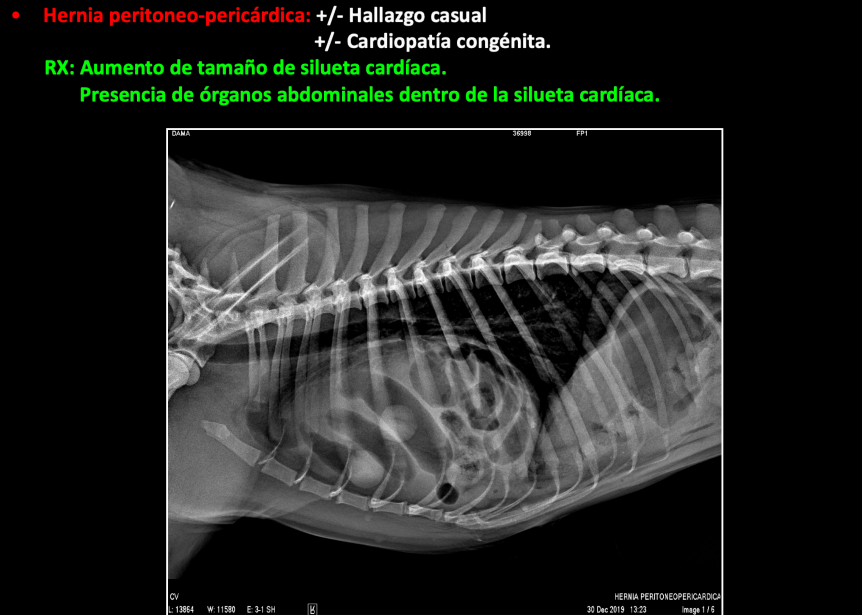

DIAFRAGMA

Hernia diafragmática:

Rotura diafragmática

Adquirida. Normalmente por traumatismo.

Desplazamiento craneal de órganos abdominales.

RX:

- Aumento de opacidad en la cavidad torácica.

- Órganos abdominales dentro de la cavidad torácica.

- Pérdida de definición del diafragma.